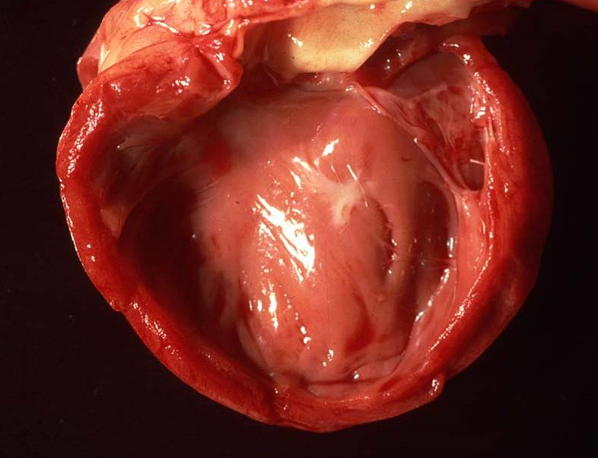

What is restrictive cardiomyopathy and when would this occur?

Walls are rigid and the heart is restricted from stretching and filling with blood properly

Rhythmicity and contractility of the heart may be normal

Stiff walls of the heart chambers keep them from adequately filling.

Cats with endocardial lesions (inflammation, fibrosis, fibroelastosis) that impair the ventricular flow

What will be seen with restrictive cardiomyopathy?